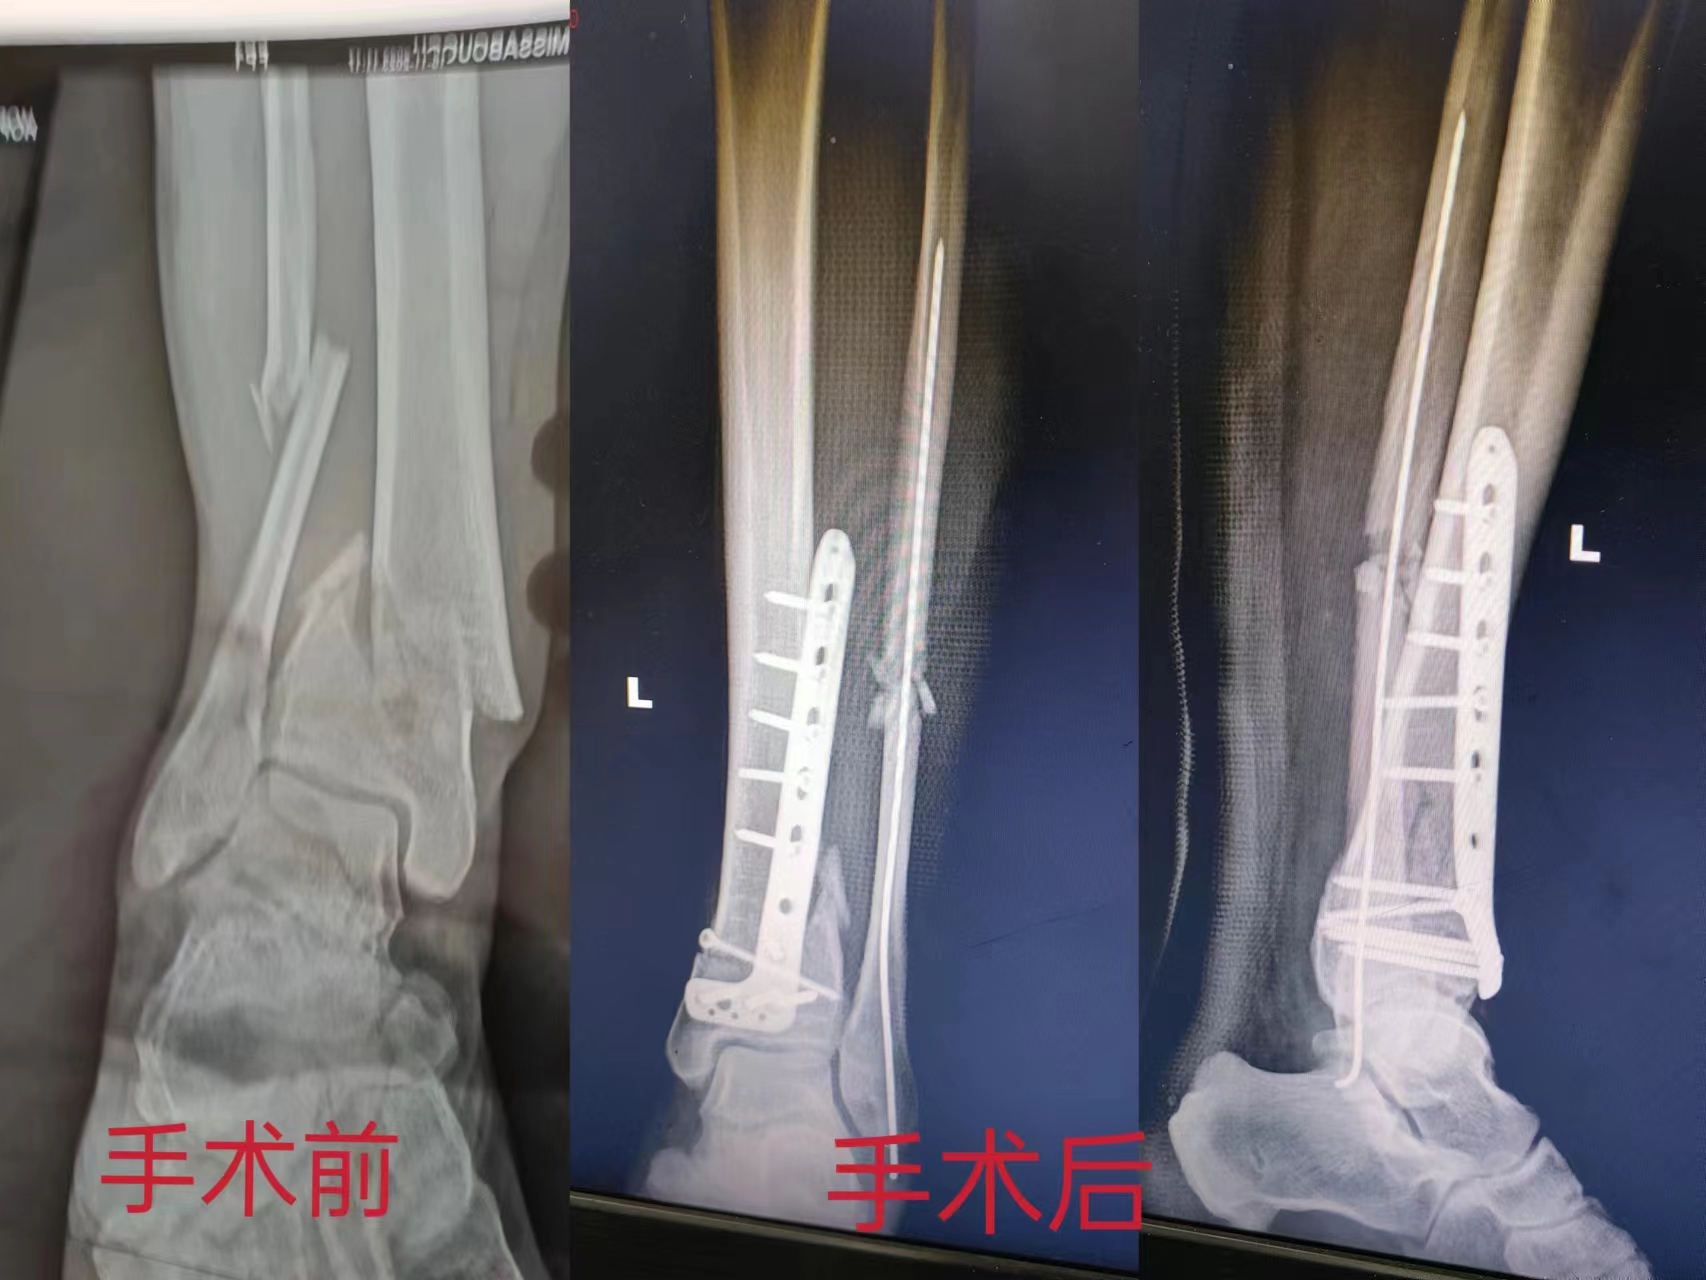

术前术后对比 夏艳 摄

回到家乡后,杨先生的亲戚朋友都建议他到桃江县第三人民医院骨科手术。入院后,该院骨科医疗团队经过详细检查和周密计划,11月28日下午,医院为杨先生成功实施了手术。术后9天后便康复出院。